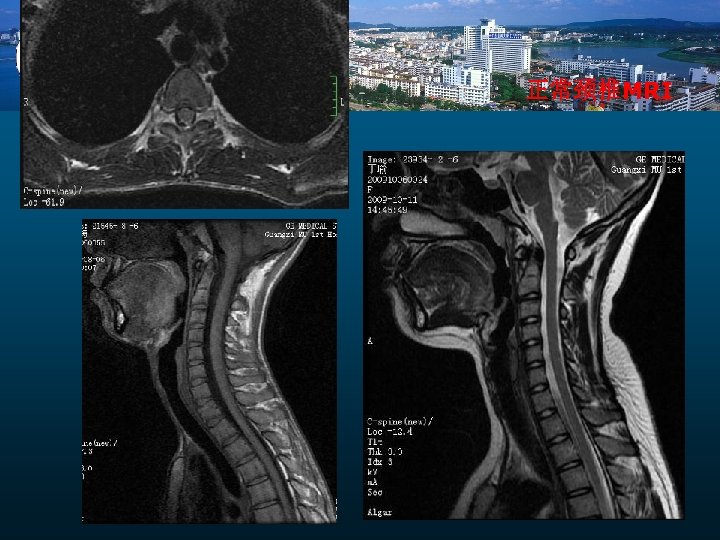

正常颈椎MRI

颈椎病的MRI检查作用 临床诊断关键 椎间盘突出 附件病变 椎管狭窄 脊髓变性 脑脊液循环障碍 自旋回波序列 快速自旋回波序列 梯度回波序列 扩散加权成像 磁化传递技术 电影相位对比技术 类PET技术 MRI诊断: 形态学变化 功能学评价

小 结 1 、X线及CT可明确显示颈椎病的骨骼改变。 2、 MRI可明确显示椎间盘变性、突出及其附件和脊髓变化, 比较全面对CSM的影像学评价. 但影像学不能轻易诊断颈椎病 3 、 椎管狭窄的MRI测量为了解CSM脊髓压迫提供客观依据 4、 PC-MR脑脊液流速测定为CSM手术效果评价提供依据